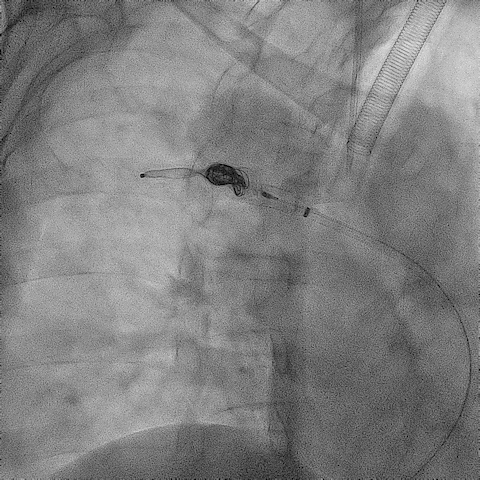

手术过程(一):

超选左肾静脉,左侧卵巢静脉,造影见卵巢静脉曲张明显,直径13 mm,盆腔大量曲张静脉显影。

图片